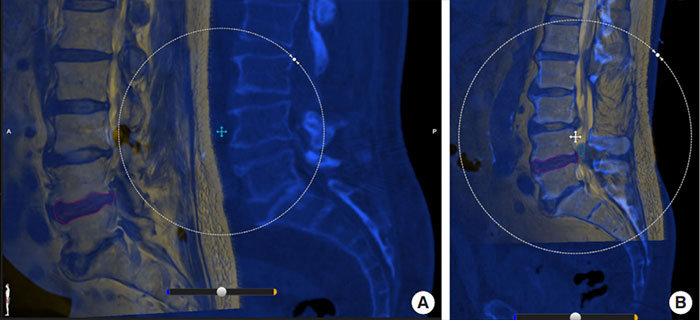

(A) Elastic image fusion of the preoperative planning MRI scan (yellow) and the intraoperative navigation CT scan (blue). (B) The scans are manually calibrated to be most accurate on the level closest to the surgical site. (Credit: Neurospine, September 2022)